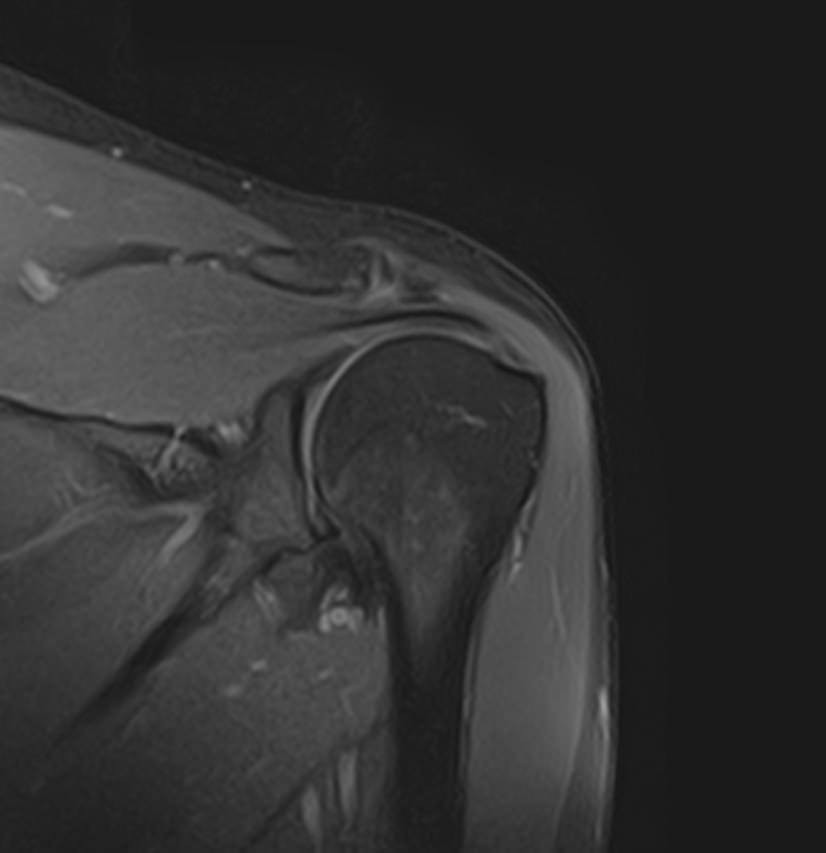

Метод МРТ позволяет оценить состояние всех анатомических областей плечевого сустава,  включая костную структуру, суставную капсулу, полость сустава с выстилающей его синовиальной оболочкой, связки, сухожилия, мышцы и окружающие мягкие ткани.

В клинике «Доступная медицина» исследование проводится на современном высокопольном томографе закрытого типа TOSHIBA VANTAGE TITAN 1,5 Тесла с превосходной  разрешающей способностью, которая обеспечивается высокой индукцией магнитного поля. Аппарат выполняет сканирование послойно в различных плоскостях и на основе этого создает 3D-изображения с высочайшей точностью и достоверностью, что позволяет эффективно ставить диагноз и назначать необходимое лечение.

Стандартная МРТ плечевого сустава не предусматривает использование контраста. В некоторых случаях для более точной визуализации патологических очагов, особенно для выявления опухолей или метастазов, может применяться контрастное усиление. Для этого внутривенно вводится контрастное вещество, в составе которого имеется металл гадолиний. Контраст избирательно накапливается в очагах поражения и обусловливает их яркое свечение под влиянием магнитного поля томографа.